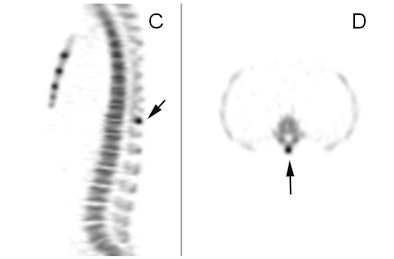

![]() |

| Images of a 15-year-old male with mid and upper back pain show increased uptake in the spinous process (A) (arrow). The condition is confirmed on the coronal (B), sagittal (C), and transverse (D) images. |